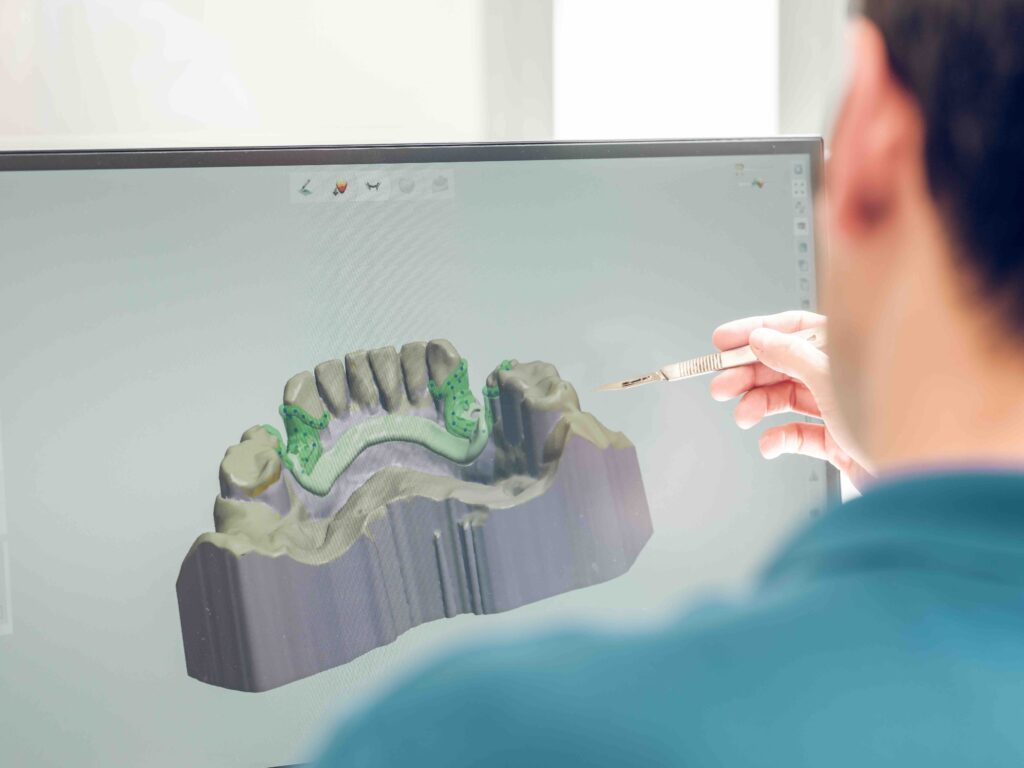

Scopri come funziona l’implantologia avanzata senza osso e quali tecniche moderne permettono di riabilitare il sorriso in sicurezza.